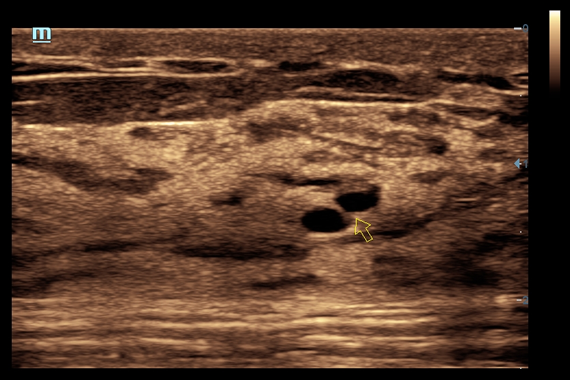

DC-60 EXP X-INSIGHT - это современный стационарный УЗИ-аппарат с функцией сенсорного управления и очищенной гармонической визуализацией, обеспечивающей лучшее контрастное разрешение и технологию 4D-визуализации. Он оснащен 21,5-дюймовым монитором, который может поворачиваться на 180 градусов, что удовлетворяет потребности врачей в качественной ультразвуковой диагностике.

• Поддержка режимов сканирования B/M/Цветовой доплер CDI/Цветной M/Энергетический доплер PD/Направленный энергетический доплер Dir.PD.

• HR Flow - режим отображения кровотока с высоким временным и пространственным разрешением для точной и однородной визуализации сосудов, в том числе самых мелких.